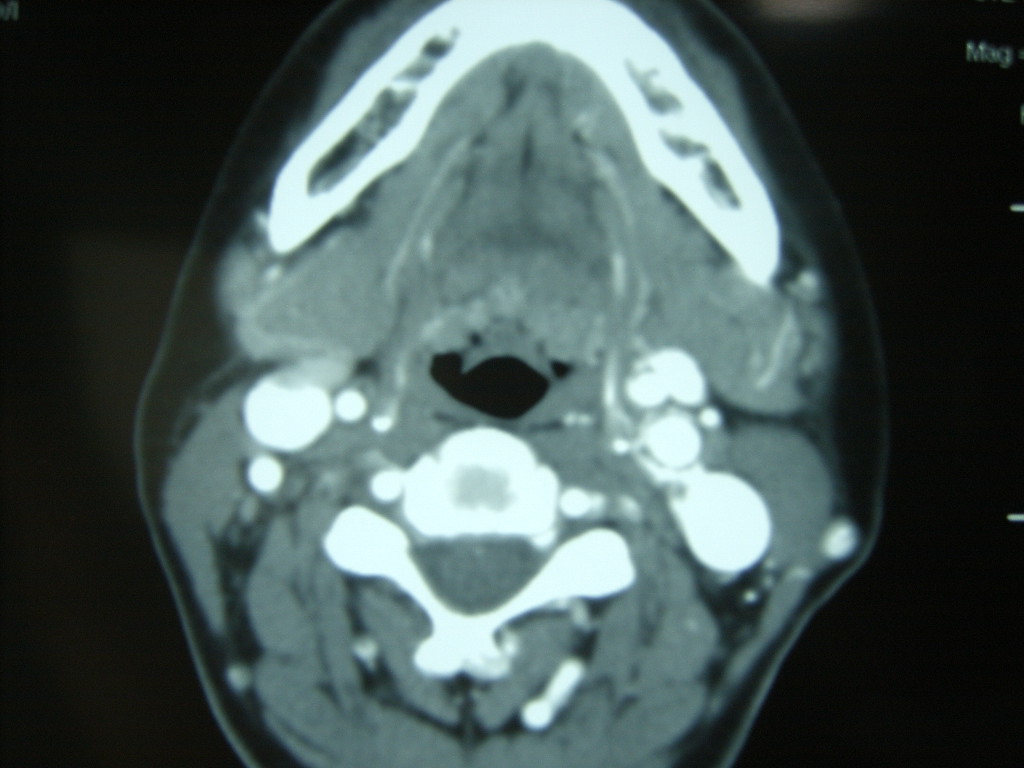

女,48岁,左颈部增粗,不适一年,伴左侧面麻.

增强明显,考虑左侧颈动脉体瘤可能性大。

答案:颈动脉体瘤  此患者已于赤峰220医院手术,